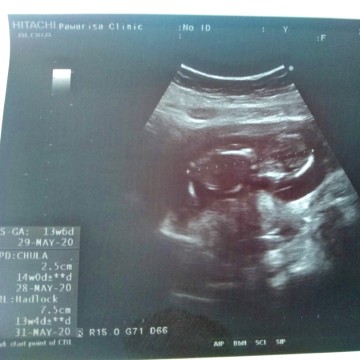

14w

ท้อง14สัปดาห์ เป้นไงบ้างค่ะ เห็นเพศหรือยัง บ้านนี้ยังไม่เห็นค่ะ น้องนอนคว่ำค่ะ

ส่วนมากยังไม่เห็นจ้า ยกเว้นเป็นผช.แล้วอ้าขาโชว์ชัดๆ